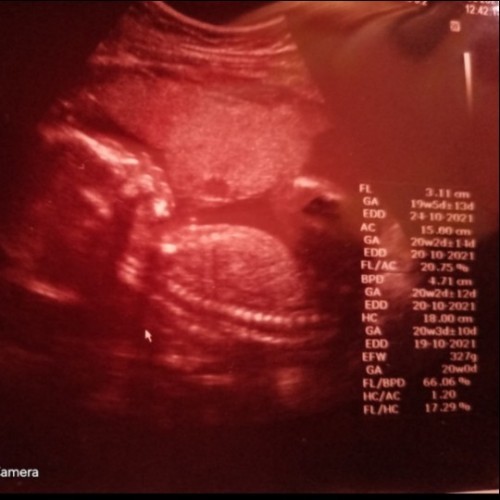

ดูที่ EDD ค่ะ จากที่ดู 9/1/65 นะคะ บางคนก็คลอดตรงกำหนด บางคนก่อน บางคนหลัง บ้านนี้เกินกำหนดมา 2 วัน ค่ะ

ทำไมของเรามีเยอะจังEDD แต่หมอนัด22. แต่ edd19-20ล่ะ งง

Eddกำหนดคลอดที่วัดจากส่วนขา Eddกำหนดคลอดที่วัดจากส่วนหัว Eddกำหนดคลอดที่วัดจากส่วนท้อง ค่ะ

EDD ค่ะ คือ Estimated Delivery Date